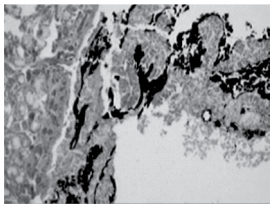

Indivíduo vítima de homicídio por arma de fogo teve seu corpo queimado com a finalidade de ocultação do corpo e, consequentemente, do crime. Durante a necropsia, foi colhido fragmento de via aérea (traqueia) cujo exame histopatológico mostrou presença de material enegrecido, compatível com fuligem, aderido ao epitélio de revestimento da mucosa, conforme mostra a figura.

É correto afirmar que